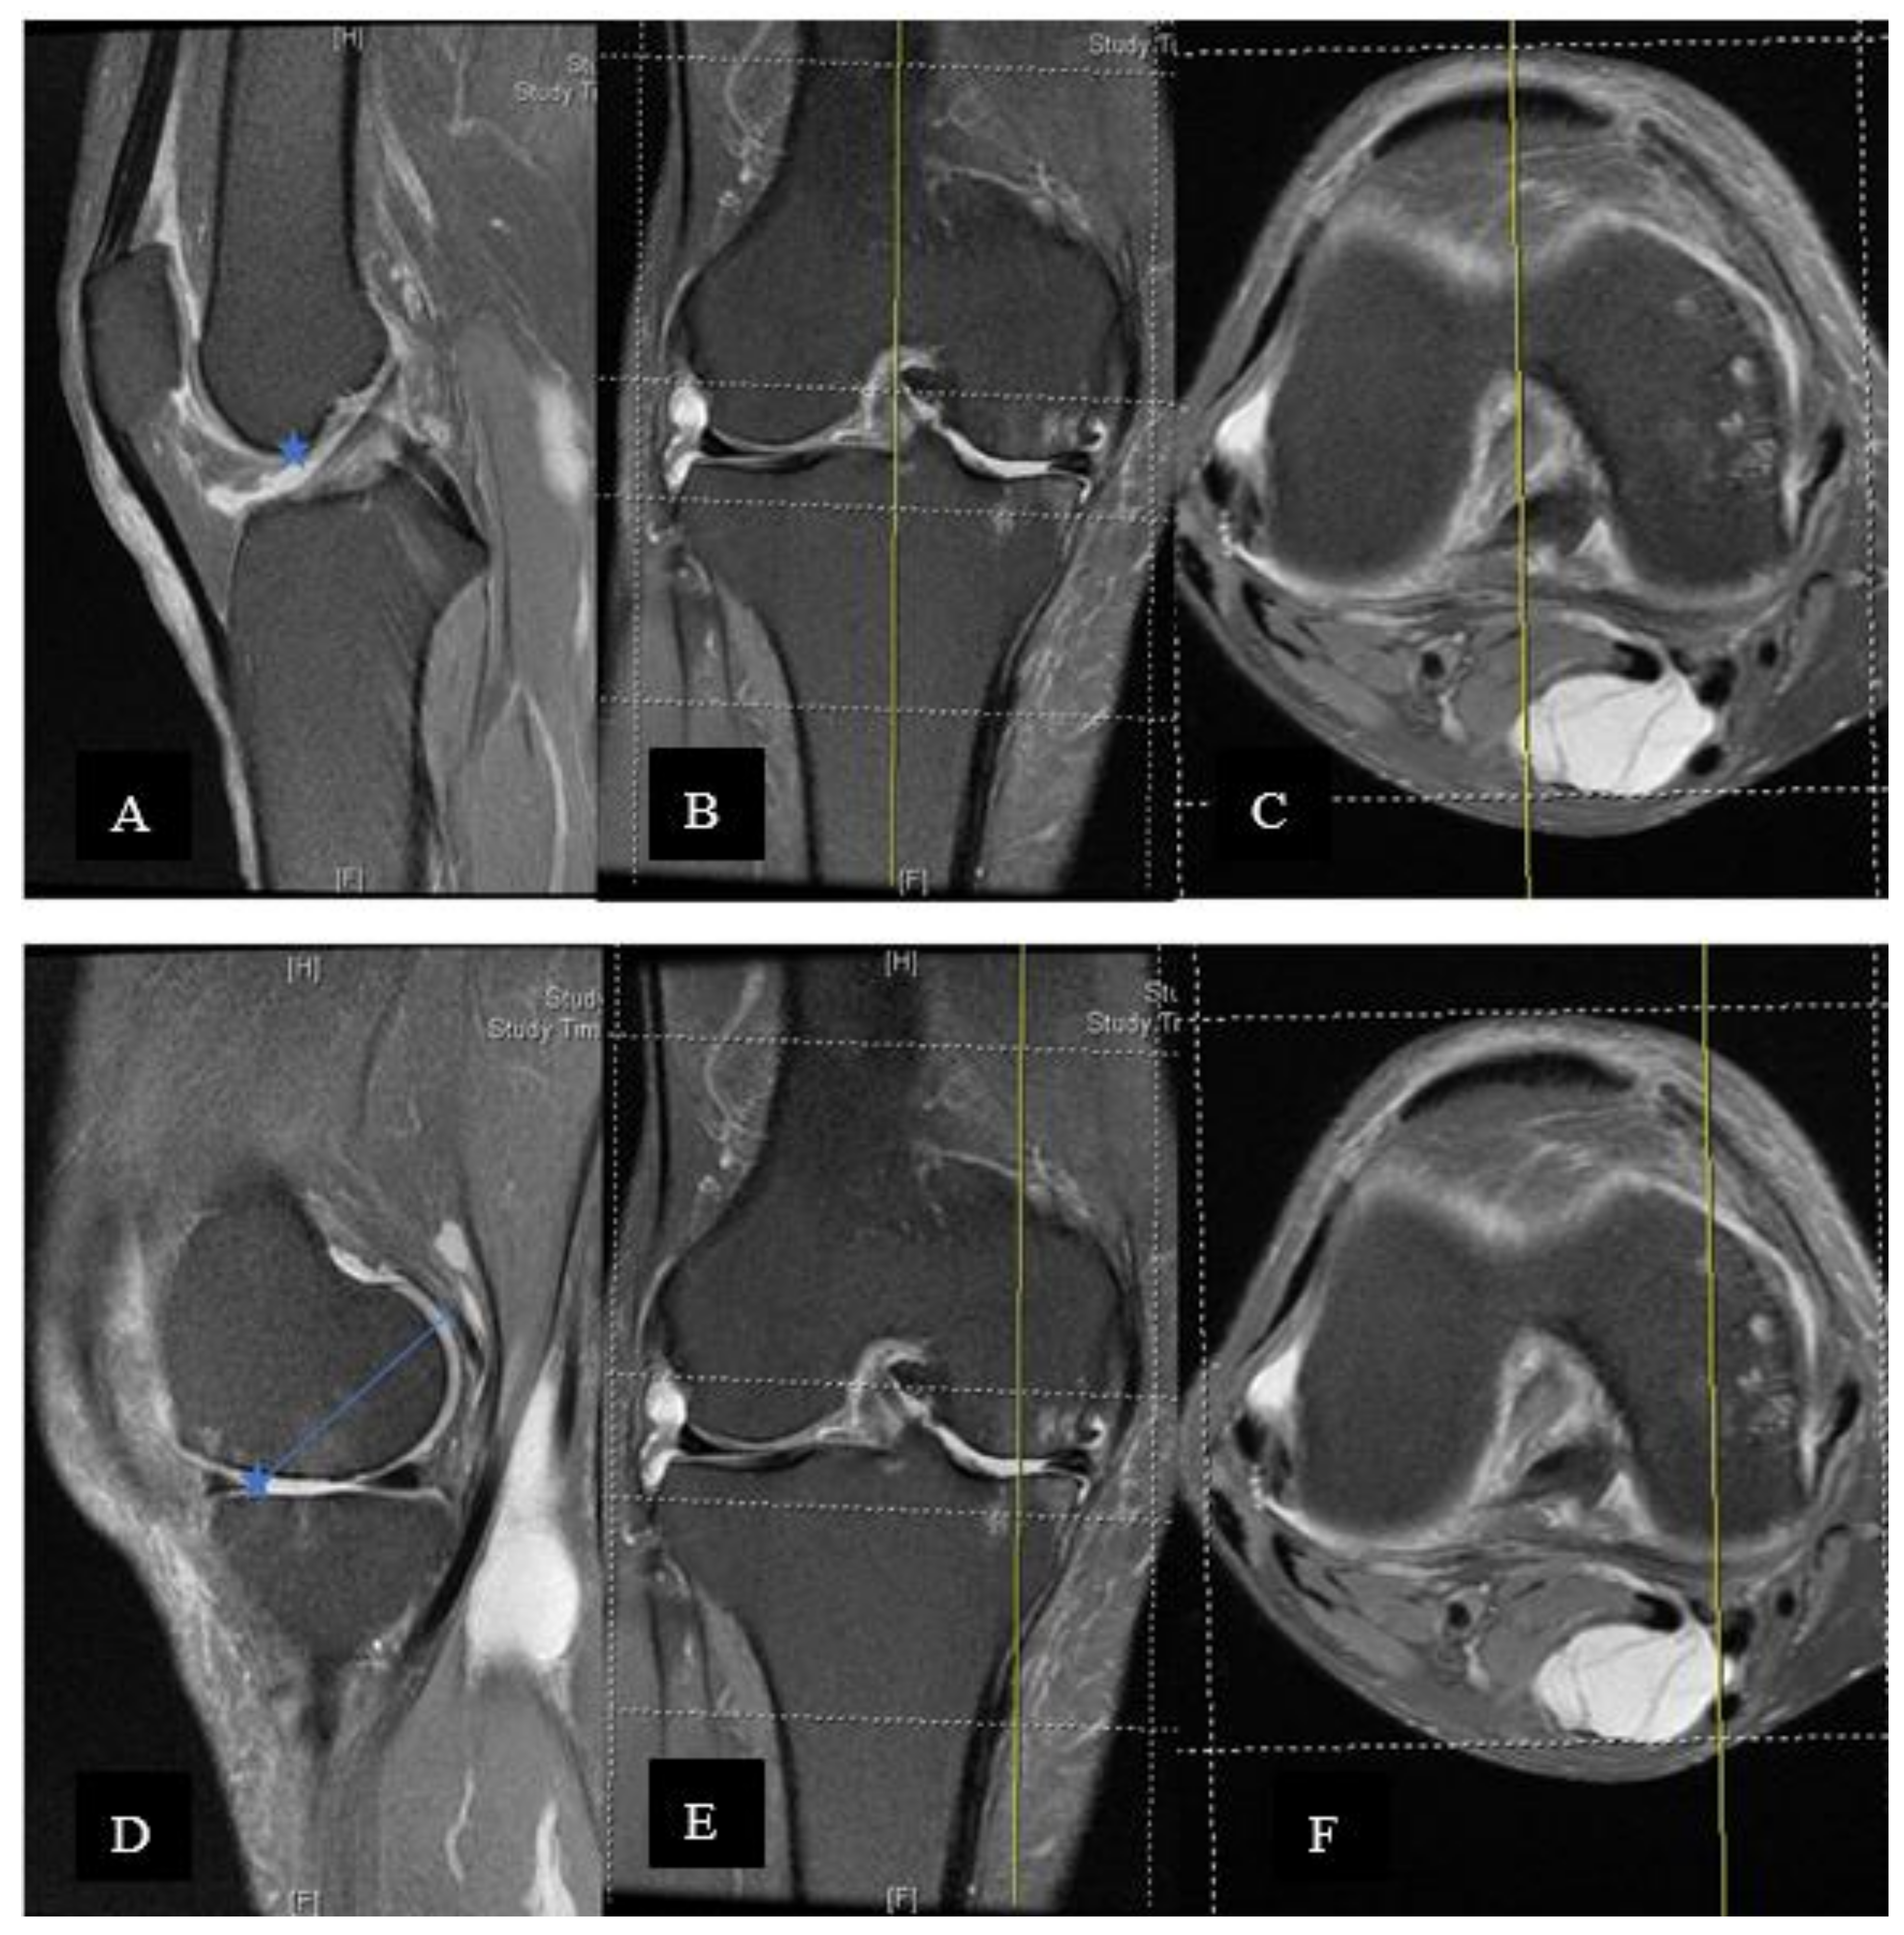

2. Materials and Methods

3. Results